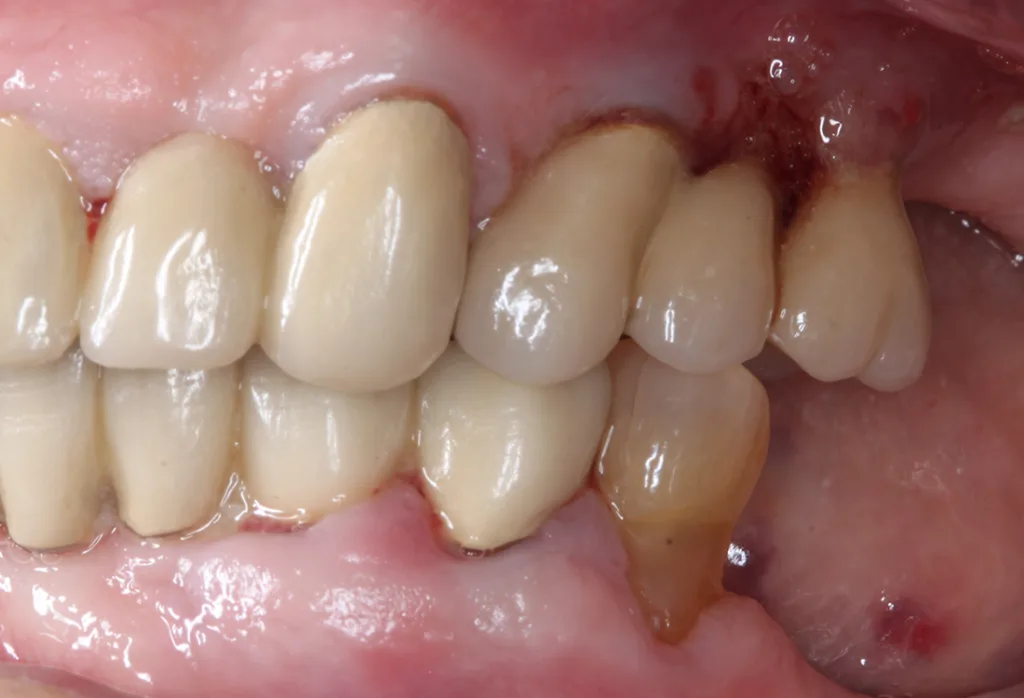

| Sekundo et al. 2020 | Periodontal and periimplant diseases in centenarians | 55/35/33 | > 60 Prozent der Teilnehmer mit eigenen Zähnenca. 4 Prozent der Teilnehmer mit Implantaten>70 Prozent der bezahnten Teilnehmer wiesen erhöhten parodontalen Behandlungs-bedarf auf |

Fast alle Befragten konnten den Wunsch nach einem Zahnarztbesuch äußern, aber ein Drittel der Teilnehmer/-innen wäre nicht mehr imstande gewesen, diesen zu organisieren [18]. Etwa 50% der Teilnehmenden hatten im vergangenen Jahr eine Zahnarztpraxis besucht und reinigten die Zähne oder Prothesen so wie vorgeschlagen zwei- bis dreimal pro Tag [18]. 20 Teilnehmer/-innen waren vollständig zahnlos [19,20]. Die Anzahl fehlender Zähne der Probanden/-innen wies eine große Varianz auf und betrug durchschnittlich 22 Zähne [20]. Von 35 bezahnten Teilnehmern/-innen [19] wiesen sieben eine weitgehend natürliche Dentition mit oder ohne festsitzende prothetische Versorgungen auf [20]. Bei sieben Patienten/-innen waren insgesamt 30 Implantate inseriert [19]. 48 Teilnehmer/-innen trugen eine herausnehmbare Teil- oder Totalprothese [20]. Etwa ein Drittel der herausnehmbaren Prothesen wurde als insuffizient (z.B. hinsichtlich Passung, Reparaturbedürftigkeit, Druckstellen oder Sauberkeit) eingestuft.

Für detaillierte parodontale und/oder periimplantäre Untersuchungen standen 33 Teilnehmer/-innen mit insgesamt 332 Zähnen (durchschnittlich 9,5 Zähne/Teilnehmer/-in) und 27 Implantaten zur Verfügung [19]. Die mittlere Anzahl von Zähnen mit moderat erhöhten Sondierungstiefen (ST ≥ 4 mm) betrug 3,9 und die mit deutlich erhöhten Sondierungstiefen (ST ≥ 6 mm) 0,7. Das bedeutete, 27,3% der Untersuchten (n = 9) wiesen keine ST ≥ 4 mm, 39,4% (n = 13) ST 4–5 mm und 33,3% (n = 11) ST ≥ 6 mm auf. Von allen 332 untersuchten Zähnen wiesen ca. 7% (n = 24) eine erhöhte Beweglichkeit auf [19]. Von den zur Untersuchung zur Verfügung stehenden Molaren (n = 59) wiesen lediglich drei Zähne einen Furkationsgrad 1 auf [19]. Drei Implantate (zwei Teilnehmende) konnten nicht weiter untersucht werden. Von den verbliebenen 27 Implantaten (fünf Patienten/-innen) wiesen 16 Implantate gesunde periimplantäre Verhältnisse auf, acht zeigten eine Mukositis und drei wurden mit Periimplantitis diagnostiziert. Der mittlere DMFT-Index betrug ca. 25 [18], und die Wurzelkariesprävalenz betrug 34,5%.

Walter/DoganDen Heidelberger Daten (HD-Z100) zufolgebesteht bei Hundertjährigen ein hoher parodontologischer, restaurativer und prothetischer Behandlungsbedarf [18–20]. In diesen Studien wurde auch die mundbezogene Lebensqualität untersucht. Demnach werteten ca. 60% der hier untersuchten Kohorte ihre orale Lebensqualität als nicht zufriedenstellend [20]. Die mundgesundheitsbezogene Lebensqualität wird dabei offenbar wesentlich durch die Anzahl fehlender Zähne beeinflusst. Im Umkehrschluss legt dies einen positiven Effekt des möglichst langen Zahnerhaltes nahe. Die kürzlich entsprechend der Leitlinien der parodontologischen Fachgesellschaft neu implementierte parodontale Behandlungssystematik dient auch diesem Ziel. Darüber hinaus ist die Lebensqualität durch festsitzenden Zahnersatz im Vergleich zu herausnehmbaren Prothesen weniger oder gar nicht eingeschränkt.

Viele der hier herausgearbeiteten Merkmale Hundertjähriger treffen tatsächlich auch auf die in den Abbildungen 6 bis 12 vorgestellte 99-jährige Dame zu. Eine weitere therapeutische Herausforderung stellt die Insuffizienz zahlreicher Prothesen dar [20]. Herausnehmbare prothetische Arbeiten erfordern regelmäßige Kontrollen und entsprechende Anpassungen. Die reduzierte Mobilität älterer und sehr alter Menschen schränkt die Möglichkeiten hierzu allerdings ein und stellt hohe Anforderungen an die aufsuchende zahnmedizinische Versorgung [30].